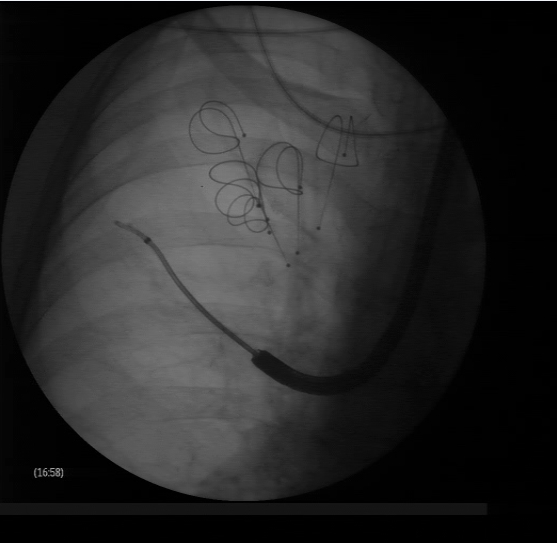

Lung volume reduction with coils: the guidewire is advanced to the targeted area